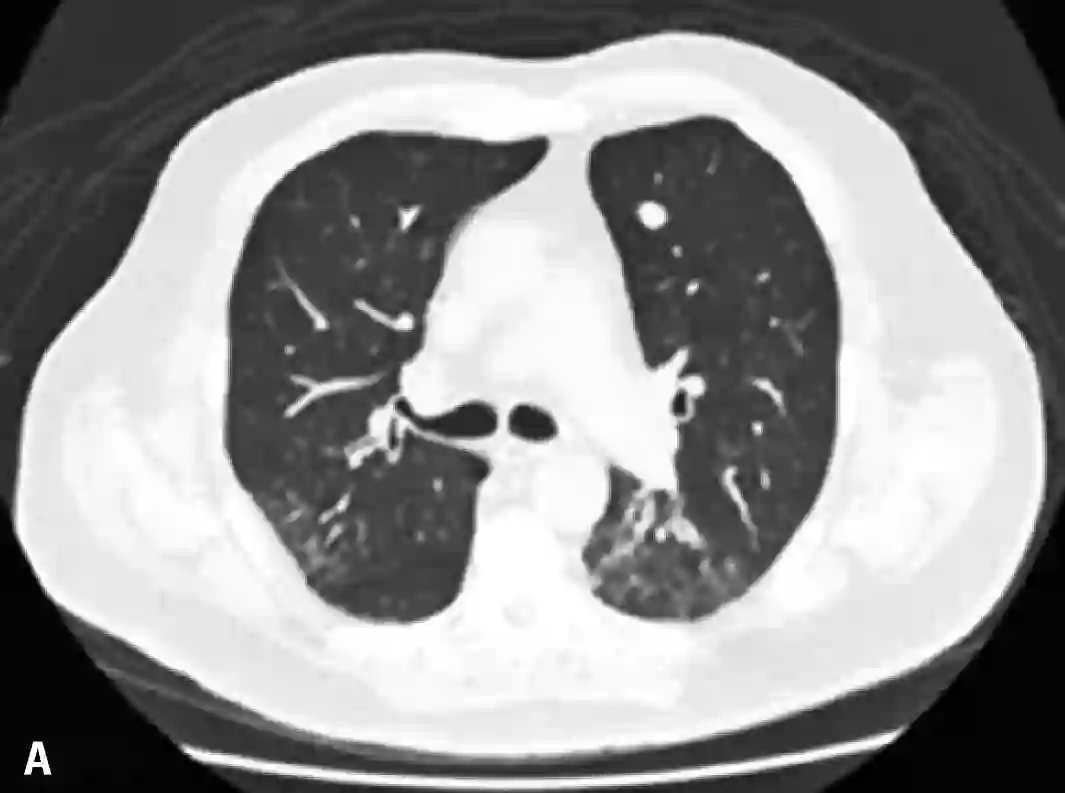

患者是一名69岁的老年男性,身患晚期转移性结肠癌,肿瘤已经转移到了肝、肺和骨组织。患者曾接受了氟嘧啶、铂、抗血管生成药、伊立替康和西妥昔单抗,但是不幸的是,所有治疗最终都没能改变病人的情况,肿瘤病情一直在持续不断的恶化,考虑到病人的实际情况,患者开始接受帕博利珠单抗(Pembrolizumabe)的治疗,每两周10mg/Kg,在第二次治疗之后,病人开始出现了发热和呼吸困难。体格检查显示,病人的血氧饱和度仅为83%,CT检查显示其左肺出现间质性肺炎,双侧胸腔都存在积液,血细胞计数显示病人的白细胞增多。为了控制肺部症状,患者在行胸腔穿刺术后,又使用了头孢曲松+克拉霉素,但是病情却并没有出现好转。CT复查显示病人的病情并没有因抗生素的使用而出现好转,反而进一步加重,双肺磨玻璃影进一步扩大。